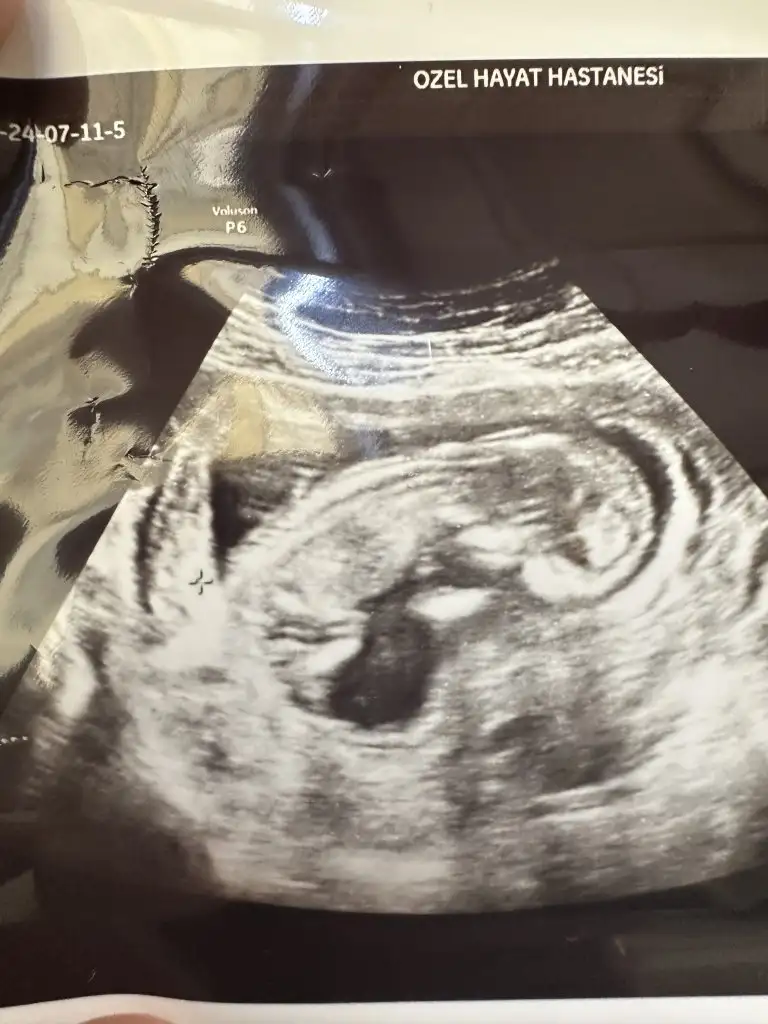

Bana da tahmin yaparmısınız